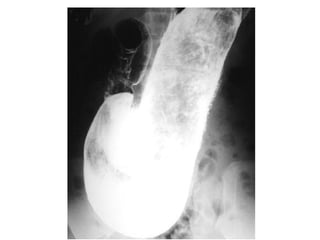

ISQUEMIA MESENTÉRICA:

• La isquemia intestinal es la

complicación más

importante de la OI, ocurre

con mayor frecuencia en

cuadros de "asa ciega" ya

descrita, hernias internas o

externas e invaginación.

• Engrosamiento parietal con

retención del contraste por

compromiso del flujo

venoso, asas que no captan

contraste vascular cuando

ya existe compromiso

arterial, neumatosis

intestinal, engrosamiento de

los vasos mesentéricos o gas

en éstos, ascitis y

neumoperitoneo

Asas con pared edematosa, llenas de

líquido, con retención del contraste y

engrosamiento mesentérico.